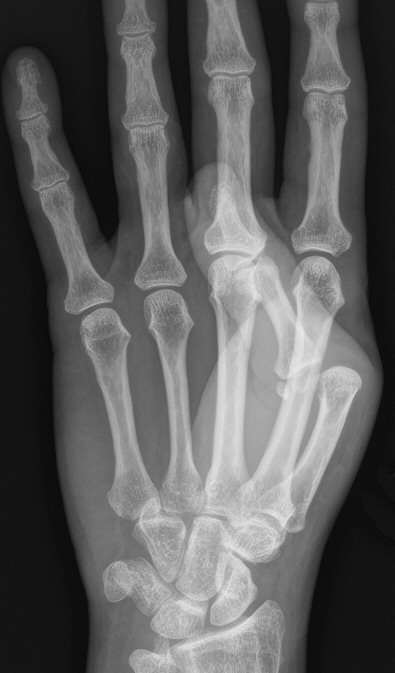

Skada: Luxation MCP-led

Kontrollera distalstatus. Utreds med slätröntgen.

Volart luxerad MCP1-led. Reponerades med axiellt drag.